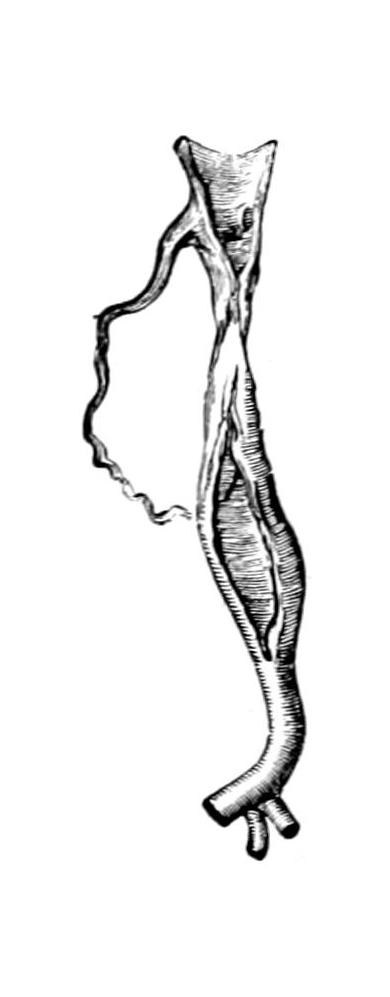

Fig. 1

Congenital hypertrophy: gigantism of both lower extremities. (Case of Dr. Graefe [Sandusky].)